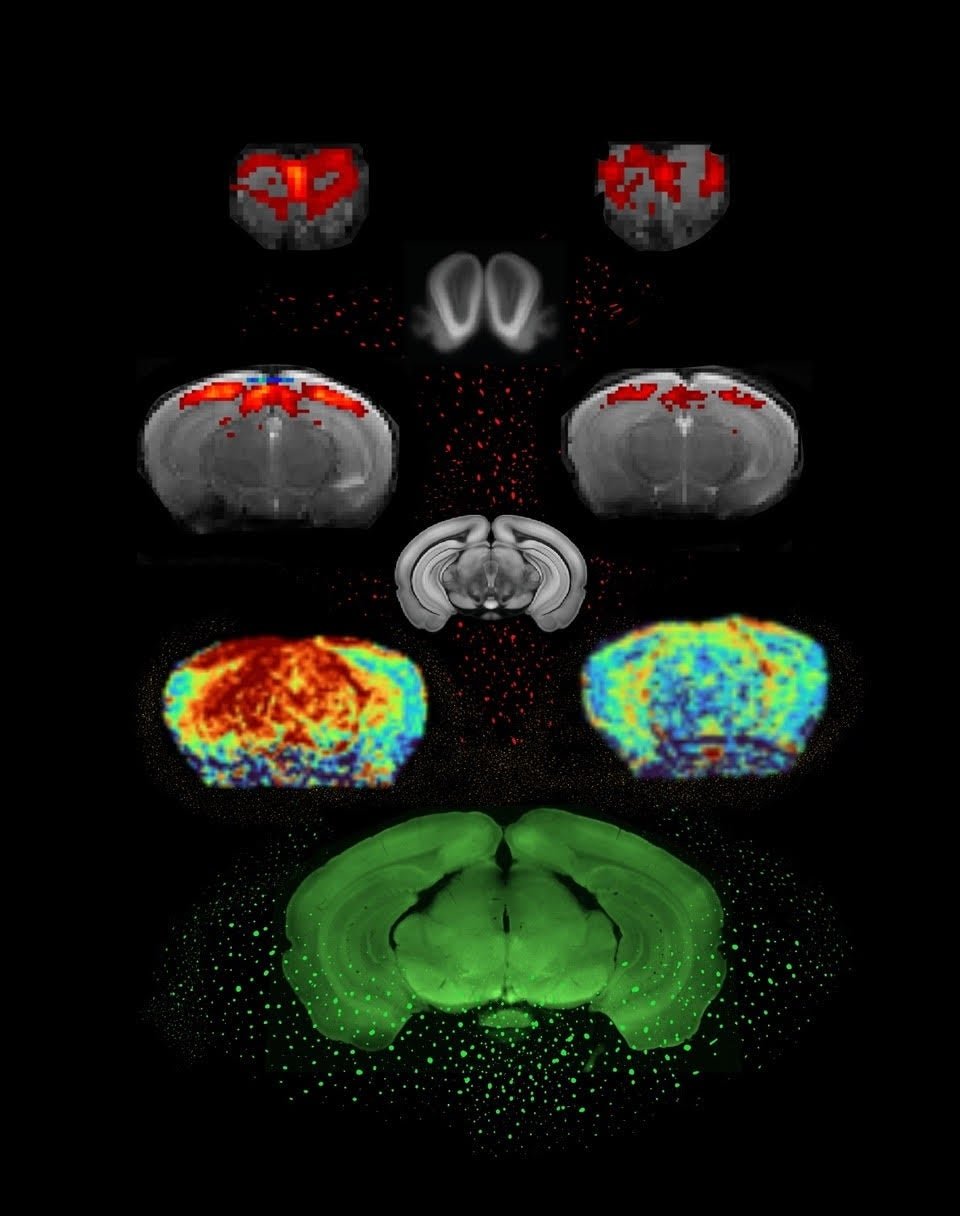

Utilizando un escáner de resonancia magnética de alta potencia (9,4 teslas, mucho más potente que los escáneres médicos convencionales de 3 teslas), los investigadores examinaron a ratones modificados genéticamente que presentaban niveles elevados de alfa-sinucleína, una proteína clave en el Parkinson. Esta proteína se acumula y forma inclusiones en la sustancia negra del cerebro, responsable de la producción de dopamina, cuya degeneración provoca los déficits motores en el Parkinson. Los ratones mostraron alteraciones en el olfato y discapacidad visual, características relacionadas con la enfermedad.

La fMRI se utiliza para observar la activación de áreas cerebrales específicas en respuesta a estímulos, como olores o estímulos visuales. Los investigadores compararon la actividad cerebral de ratones que produjeron ovillos de alfa-sinucleína con los de control, demostrando que los ratones con Parkinson mostraban una actividad cerebral reducida en comparación con los controles.

Aunque la fMRI no mide directamente la actividad neuronal, los investigadores también utilizaron técnicas adicionales para diferenciar entre los efectos neuronales y vasculares. Al analizar la actividad neuronal a través de una proteína llamada C-FOS, los resultados mostraron que la reducción de la actividad neuronal en los ratones con Parkinson era más pronunciada que los efectos vasculares, lo que sugiere que los cambios observados en las imágenes fMRI se debieron principalmente a alteraciones neuronales.